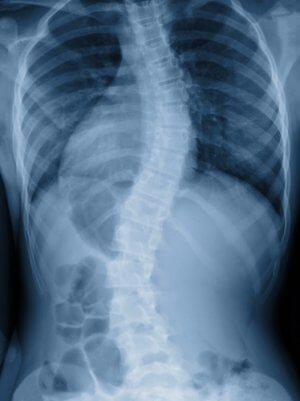

Причины развития сколиоза у детей и у взрослых разные. У детей, как правило, это врожденная патология или следствие неправильной осанки, у взрослых – результат дегенеративных изменений межпозвоночных дисков, обусловленных возрастом. Поэтому подход к лечению диктуется не только степенью тяжести болезни, но и возрастом пациента.

Консервативное лечение детского сколиоза. В некоторых случаях, если речь идет об осаночных сколиозах, врач может предпочесть какое-то время понаблюдать за течением болезни. Неправильную осанку при 1-2 стадии сколиоза можно исправить путем специальных упражнений, которые укрепляют мышцы и развивают их гибкость. Методы лечения сколиоза у детей учитывают тот факт, что зоны роста скелета у ребенка еще открыты, поэтому важно использовать те лечебные средства, которые не препятствуют росту позвоночника. Консервативное лечение заключается в ношении специально разработанного реклинатора – повязки, которая вырабатывает привычку держать спину и плечи в правильном положении и исправляет осанку. Реклинатор представляет собой конструкцию из лямок, которая надевается на спину, как ранец. При более серьезных искривлениях может быть назначено ношение фиксирующего корсета, подобранного индивидуально, с учетом анатомических особенностей ребенка. Корсет конструируется таким образом, чтобы возникало давление на те области позвоночника, которые искривлены, этим самым исправляется деформация.

Хирургическое лечение сколиоза 4 степени в Израиле детям назначается в том случае, когда способы консервативной терапии неэффективны. Если болезнь быстро прогрессирует, ребенок испытывает боли, не может нормально передвигаться, если у него из-за деформации позвоночника уменьшается объем легких, хирурги выполняют операцию по фиксации расположенных рядом позвонков. Лечение сколиоза 4 степени в Израиле оперативно проводится и для взрослых: методы, которыми проводятся подобные операции в клинике СТС, считаются самыми прогрессивными в мире. Во время проведения операции осуществляется постоянный мониторинг при помощи инновационного оборудования – спинальной нейронавигационной системы O-Arm. Специальный встроенный сканер делает снимки оперируемого участка с разных ракурсов, под разными углами, в 3D-формате. Это дает возможность хирургу отслеживать ход проведения операции и правильность выполняемых им действий. Система O-Arm позволяет свести к нулю риск врачебных ошибок. Сразу же после того, как проведено вмешательство, система фиксирует достигнутый результат.